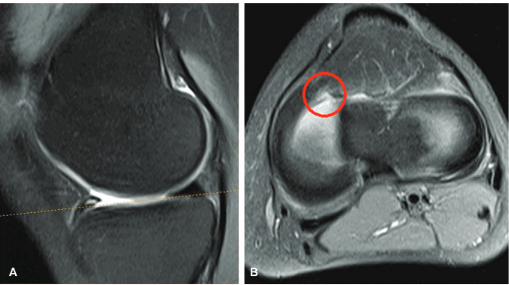

Мениско-бедренные связки(передняя–Humphrey,задняя–Wrisberg)являются вспомогательным удерживателем наружного мениска вследствие слабой фиксации к суставной капсуле, начинаются от заднего рога и фиксируются у латерального края внутреннего мыщелка бедраили задней крестообразной связки, вместе встречаются в трети случаев, одна из них – в 93 %. Дифференциальный диагноз проводится с целью исключения краевых разрывов заднего рога латерального мениска, имитация которых возможна на сагиттальных срезах в области прикрепления. Для подтверждения нормы необходимо отследить связку на протяжении серии сагиттальных кадров в виде четкого ровного поперечника, а также сопоставить с данными, полученными во фронтальной плоскости, где становится возможным дифференцировать ее интактный ход относительно плоскости мениска.

В редких случаях гипертрофированная связка Humphrey в сагиттальной плоскости имитирует смещенный лоскут мениска по типу «ручки лейки», определяясь в виде дупликатуры задней крестообразной связки, однако при совмещении с фронтальной плоскостью подозрительная структура интактна относительно плоскости мениска (в журнале «Skeletal radiology» такое состояние описано в виде симптома «Pseudo- double PCL sign» [10, 17, 18, 19] (рис. 5).